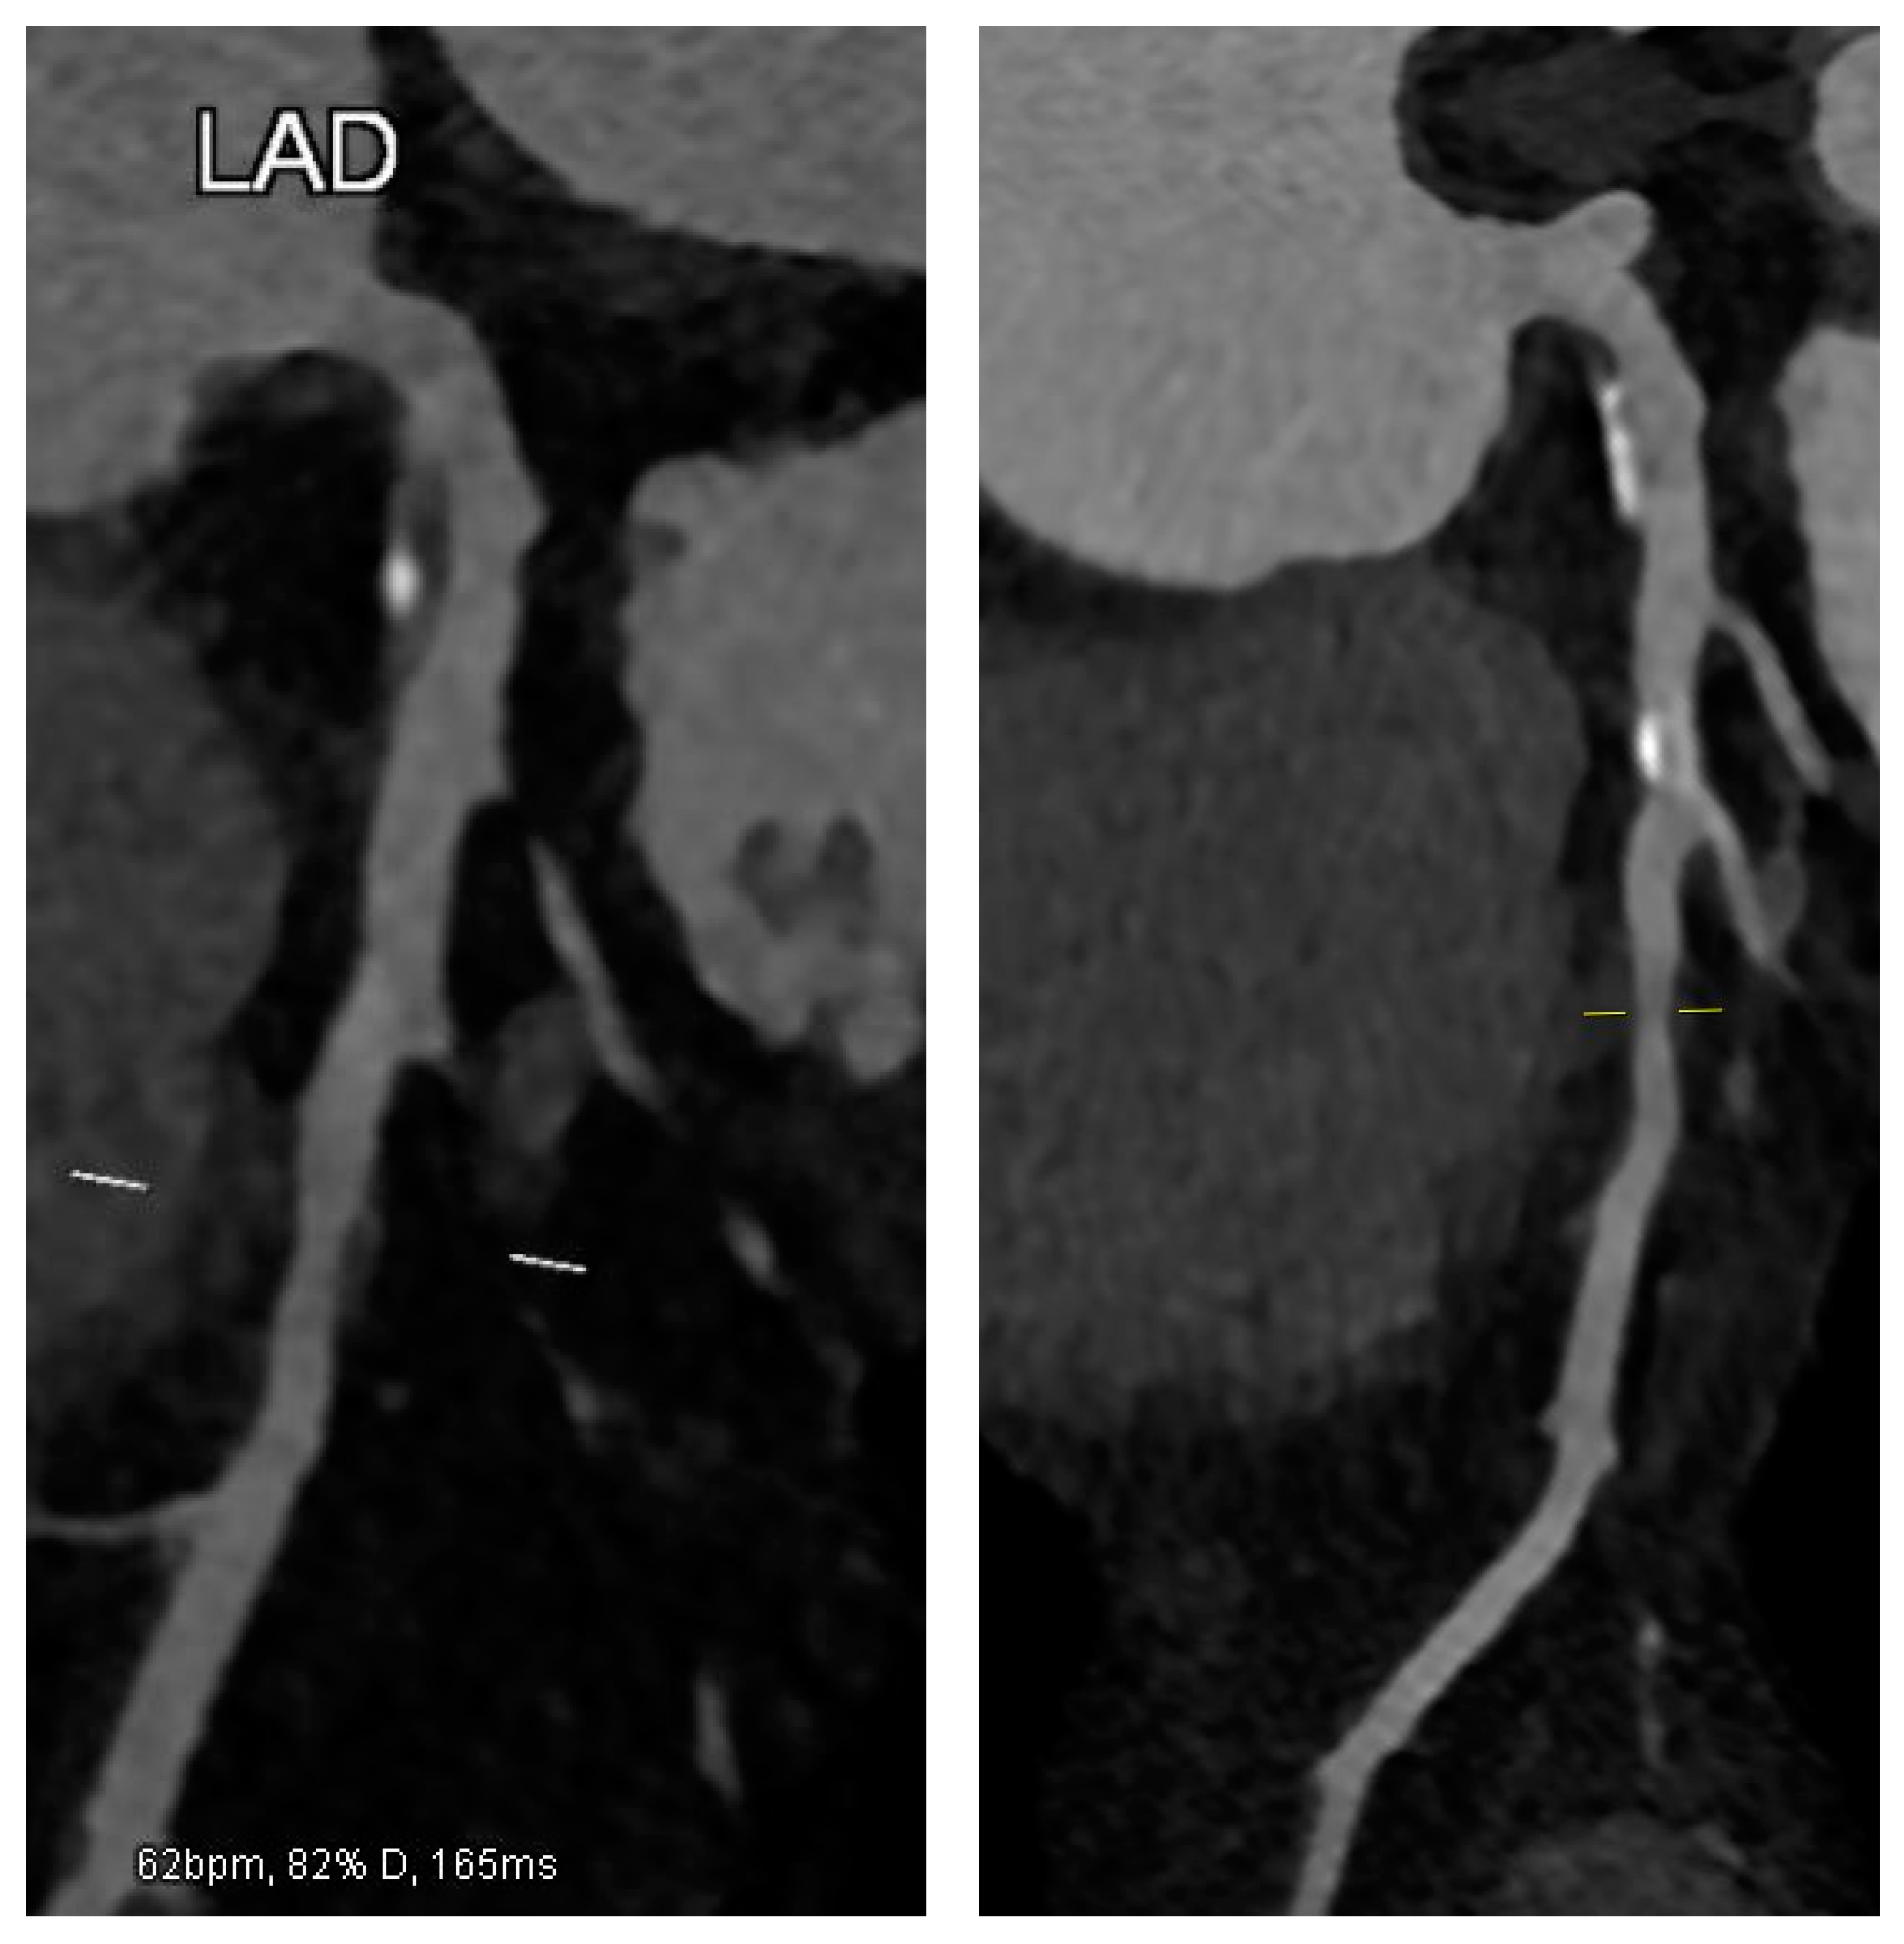

A 50-year-old male with chronic coronary syndrome presented after a recent inferolateral myocardial infarction (MI). His history included a prior posterolateral STEMI, treated with PCI and stenting of a culprit lesion in the Cx. A non-significant yet non-negligible (approximately 50%) ostial LAD stenosis was observed but not further evaluated with IVUS or OCT. His cardiovascular risk factors included mixed dyslipidemia (pre-admission LDL-C: 123 mg/dL), hypertension, overweight status, and a history of smoking, which he quit post-MI. At baseline (within 30 days), he was prescribed Bisoprolol, Ramipril, Ticagrelor, Aspirin, and Atorvastatin 80 mg daily. Despite occasional non-adherence, he reported exertional dyspnea without chest pain. Due to an LDL-C of 94 mg/dL, therapy was switched to Rosuvastatin plus Ezetimibe, with adherence counseling. At three months, echocardiography showed preserved LV function with localized hypokinesia of the posterolateral wall. The patient reported good compliance, achieved an LDL-C of 54 mg/dL, and remained asymptomatic. A follow-up was planned within a year. At 12 months, LDL-C rose modestly to 71 mg/dL, slightly above target, attributed to mild weight gain from a suboptimal diet despite reported adherence. To refine risk stratification, CCTA was selected as the imaging modality of choice, aligned with current guidelines [7,8]. An ECG-gated CCTA was performed using a single-source 128-slice CT scanner (Somatom go. Top 128, Siemens, Germany). The patient was hemodynamically stable, with a heart rate < 60 bpm after infusion of Metoprolol. Nitroglycerin was administered for optimal coronary visualization. Imaging was acquired in a single end-inspiratory breath-hold, covering the area from the carina to the diaphragm. A total of 70 mL of high-concentration iodinated contrast (370 mgI/mL) was injected at 5 mL/s, followed by 40 mL of saline at the same rate. Retrospectively ECG-gated imaging was triggered by ascending aortic opacification (>150 HU). Axial images were reconstructed at a 0.4 mm slice thickness using iterative methods. High-risk plaque (HRP) parameters included low-attenuation plaque (LAP), spotty calcification (SC), and positive remodeling (PR). LAP was defined as any pixel with HU ≤ 30 within the lesion. SC was a small (<3 mm), dense (>130 HU) plaque component surrounded by non-calcified tissue. PR was defined by a remodeling index ≥ 1.1 (maximal lesion vessel area/proximal reference vessel area). A CT scan revealed a high-risk plaque in the proximal LAD, characterized by a predominantly non-calcified component, low-attenuation, positive remodeling, and spotty calcifications, all indicative of plaque vulnerability (Figure 1). In response, the therapeutic strategy was adjusted: Ticagrelor was reduced (not discontinued), and Evolocumab (140 mg SC every two weeks) was introduced. The patient was counseled on a lipid-lowering diet and regular aerobic exercise. At 24 months, the patient remained asymptomatic, with stable weight and good adherence to therapy. Echocardiography showed unchanged LV function. LDL-C was significantly reduced to 18 mg/dL (Figure 2). A repeat CCTA using the same protocol, operator, and scanner revealed a transformation in plaque phenotype, with the high-risk plaque evolving into a predominantly calcified form and an increased vessel lumen, indicative of greater stability and lower rupture risk [9,10]. Plaque volume, stenosis, and positive remodeling were substantially reduced (Figure 1). Based on these findings, the therapeutic regimen was maintained, except for Ticagrelor discontinuation. A follow-up was scheduled within one year or earlier if symptoms developed.

Figure 1. CCTA reveals a high-risk mixed plaque in the proximal LAD with a predominantly non-calcified component (left). After Evolocumab therapy, the plaque transforms into a more calcified, stable phenotype with reduced volume (right).